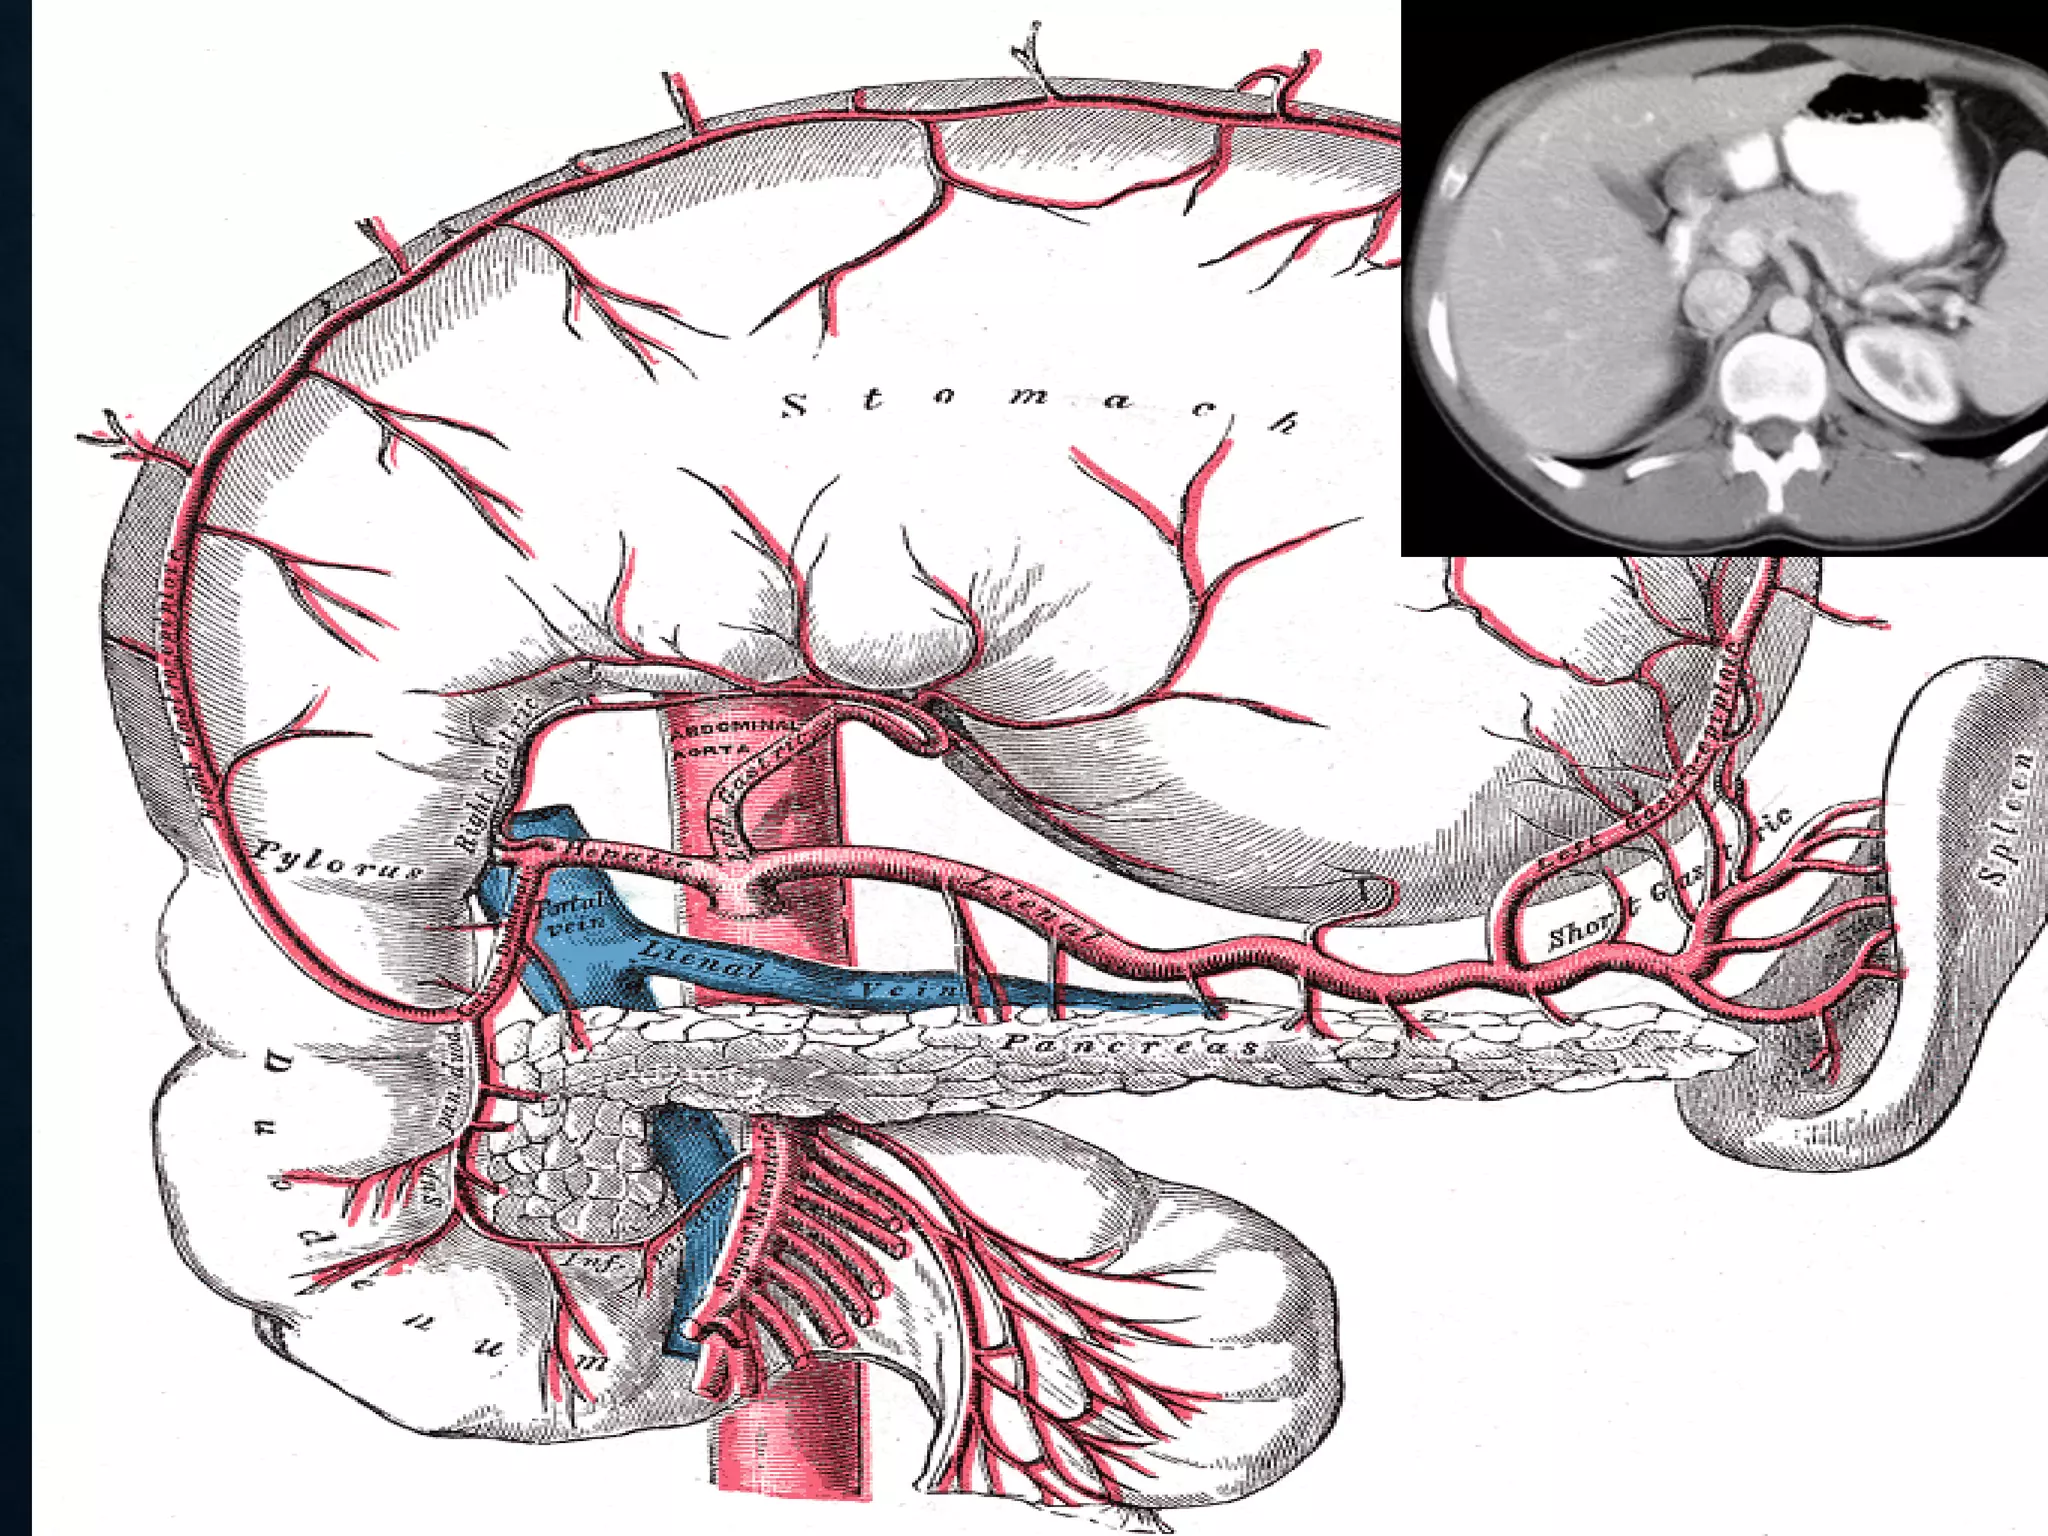

CELIAC

• Branching from the aorta 'anterior to the

T12‘ one of three anterior/ midline branches of the

abdominal aorta (the others are the superior and inferior

mesenteric arteries).

CELIAC ARTERY BRANCHES

• Left gastric artery

• Common hepatic artery

• Splenic artery

CELIAC • Branching fromthe aorta 'anterior to the T12‘ one of three anterior/ midline branches of the abdominal aorta (the others are the superior and inferior mesenteric arteries).

CELIAC ARTERY BRANCHES •Left gastric artery • Common hepatic artery • Splenic artery

SUPERIOR MESENTERIC VEIN •In anatomy, the superior mesenteric vein (SMV) is a blood vessel that drains blood from the small intestine (jejunum and ileum). • At its termination behind the neck of the pancreas, • the SMV combines with the splenic vein to form the hepatic portal vein. • The SMV lies to the right of the similarly named artery, the superior mesenteric artery, which originates from the abdominal aorta.